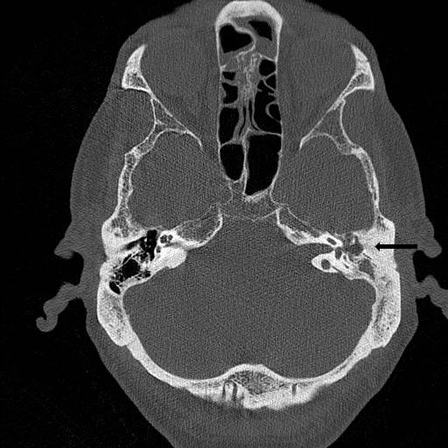

- TC de ossos petrosos temporais:

deiscência óssea do canal semicircular superior no lado afetado